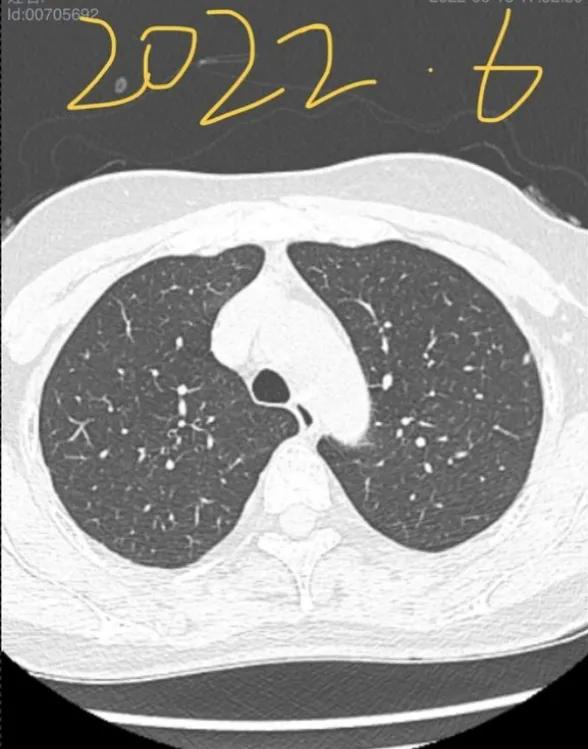

一个安徽的宝妈,在6月的时候向我求助:她的妈妈CT查出了两处磨玻璃结节,尺寸都在6-7mm。后来随访过程中发现一个结节增长到了10mm,并且出现了侵犯胸膜的情况,加上省会医生给的一个“微浸润”,这下让这位宝妈异常焦急。再次向我求助,想来重庆新桥进行手术。(插一句,我对宝妈这样质实的孝,异常钦佩;对于宝妈的要求,我一定是安排好所有的绿色通道,亲自处理的)。手术很成功,虽然难度极大(全胸腔粘连),但是考虑到患者未来恢复,和你需要照顾孩子的实际情况,我还是坚持全程微创,没有开胸。手术即治愈,未来慢慢恢复即可,不用担心。

2021年12月,我母亲做CT查出左肺上下叶各有一磨玻璃结节,大小均为6-7mm,医生让3-6月复查。今年6月复查,报告显示有一个侵犯胸膜,大小长至10mm。医生看影像后初判微浸润,让手术切除。慕名而来,恳请戴主任帮忙看看,我们好心安。

大的结节早期浸润性腺癌,小的结节原位或良性的。楔形切除小手术即可搞定。4mm的可以不切